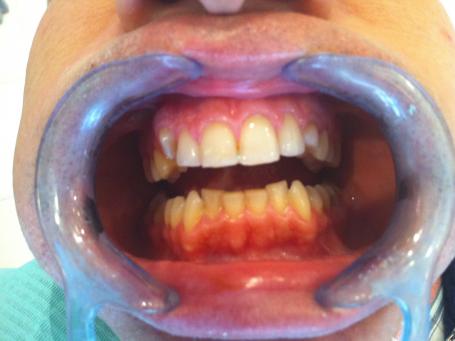

1°)Photo initiale.

Un patient se présente au cabinet dentaire à cannes croisette suite à une fracture de l’incisive centrale droite.

Un composite de substitution est réalisé en urgence pour restaurer l’esthétique.

Des doléances esthétiques sont mises en avant lors de cette consultation d’urgence .

Une canine de lait persiste à gauche tandis que la canine de droite présente une éruption incomplète et arrêtée.